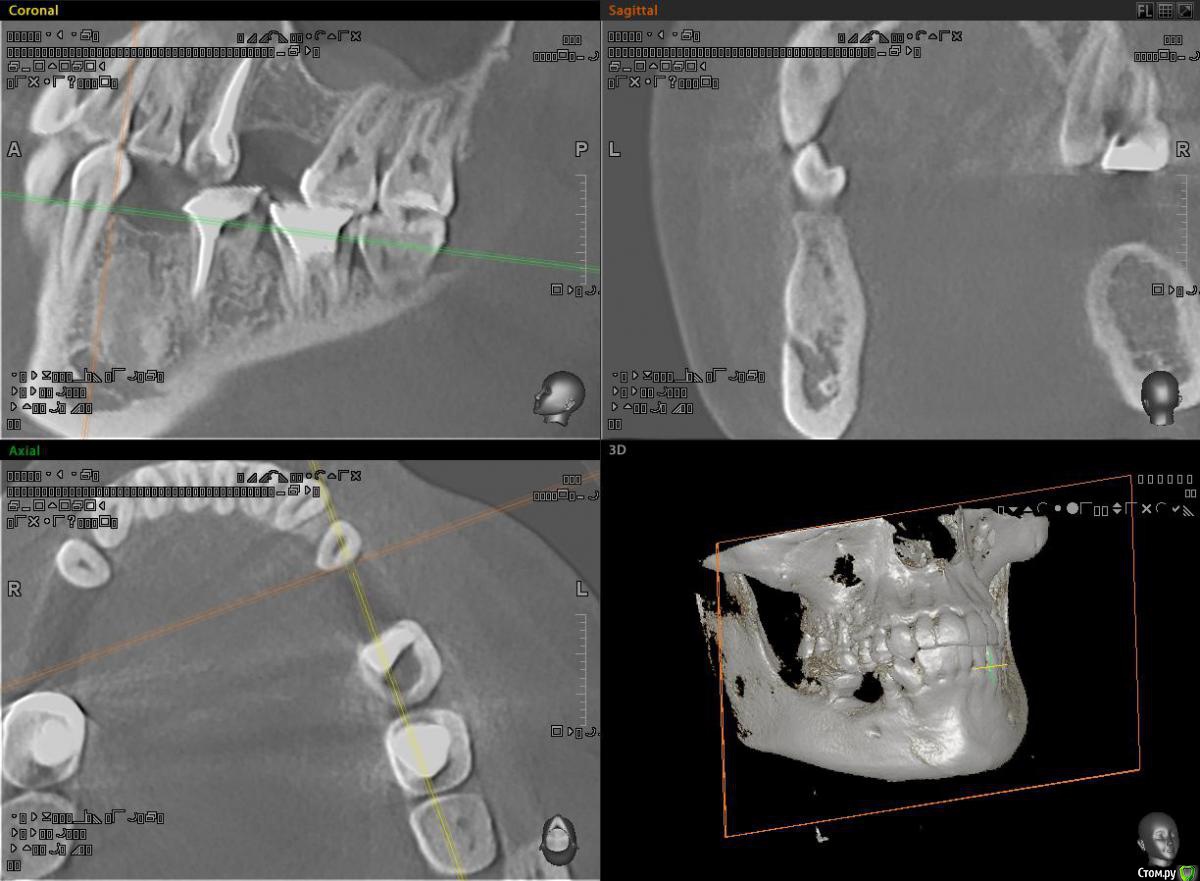

alekszander Опубликовано 16 декабря, 2015 Поделиться Опубликовано 16 декабря, 2015 Почитал тему про цементомы и посмотрел, чтов зависиости от года тактика менялась))Направлен пациент на возможность имплантации в области зуба ... ну назовем его 3.6.На Кт вот такой рисунок кости. Как понимаю, максимум что там было - молочный зуб,т.к. 4.6-4.8 на месте.1. Есть ли смысл туда сверлиться?2. Есть ли смысл отправить на гистологию,если не будем сверлиться и ортопед поставит мост?3. Главный вопрос Что это? Цементома? Ссылка на комментарий

ILGAMSA Опубликовано 16 декабря, 2015 Поделиться Опубликовано 16 декабря, 2015 Это не цементома, это участок остеосклероза. 2 Ссылка на комментарий

Доктор Дмитрий Опубликовано 16 декабря, 2015 Поделиться Опубликовано 16 декабря, 2015 Качество снимков не очень, может настройками можно подкорректировать Ссылка на комментарий